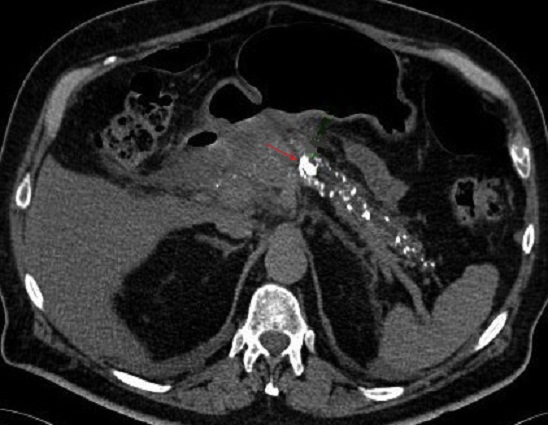

De meme cas en

coupe TDM axiale . Pancreas en volumineuse , a bord

irregulier en presence des calciofications et

depots hyperdence de tonalite calcique

parenchymateuse . Pancreatite chronique primitive |

Les calcifications souvent

parenchymateuse mais parfoi peut etre canalaire (

fleche rouge ). Dans ce cas image de dilatation des

canal biliaire peut en voyait . Image

radiologique TDM d'une pancreatite chronique +

calcul du canal pancreatique en coupe axiale |